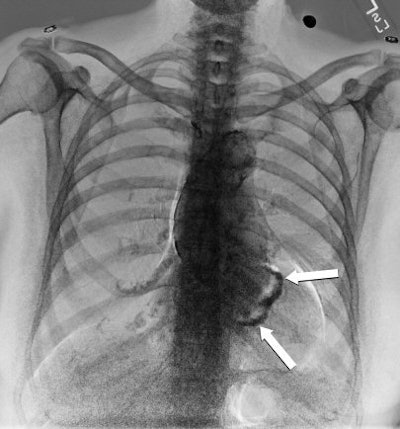

Gilkeson sees dual-energy subtraction as a potentially useful tool in detecting cardiovascular disease, primarily in the viewing of calcium in coronary arteries and serving as a "screening tool or opportunity to look at coronary artery disease in a noninvasive way."

"There is no doubt that you see calcium in coronary arteries in dual-energy that you don't see off a standard x-ray," he said.

At the very least, Gilkeson added, the detection of calcium should prompt a radiologist to alert a referring physician to the possibility of coronary artery disease in a patient with chest pain.

| Dual-energy bone image of figures above. The mitral annular calcifications are demonstrated (arrows). All images courtesy of Dr. Robert Gilkeson and medical student Sonali Mehandru, University Hospitals in Cleveland. |